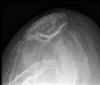

Fractura impactada de húmero .